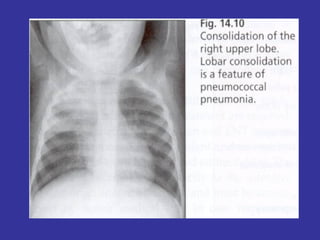

PNEUMONIA  Inflammation and infection of the lung parenchyma due to bacterial or viral  pathogens. Classified by anatomy:  Lobar, Interstitial, Bronchopneumonia Etiology: Viral:   Adenovirus, Influenza, RSV Bacterial:   Neonates:  GBS, Chlamydia, E. coli, Listeria monocytogenes  1month-6 years:  S. pneumonia, H. influenza Adolescents:  S. pneumonia, Mycoplasma pneumonia Immunocompromised:  Pseudomonas, klebsiela, Fungi, PCP

Epidemiology:   Children 2-4 years, are more susceptible than older children May follow epidemics of viral infection Winter/spring most common Day care/ kindergarten S/S:   Tachypnea,  dyspnea,  cough,  intercostal retractions, nasal flaring,  grunting,  fever,  accessory resp. muscles usage,  chest pain,  lethargy,  hypoxia, rales/crackles,  decreased  breath  sound/dullness to percussion (consolidation). LAB:   CBC:   WBC with left shift,  Blood culture (if severe picture),  Pleural fluid studies (effusion),  ABG  CXR:   Lobar consolidation ( S. pneumonia and H. influenza ),  Hilar adenopathy ( TB ),  Pneumatoceles ( S. aureus/G- ),  Bilateral diffuse infiltrate ( Mycoplasma ),  Abscess ( klebsiella ) Mycoplasma:  Presence of Cold agglutinin titers Prevention:   Pneumovax vaccine in immunocompromised children, SC Ds.